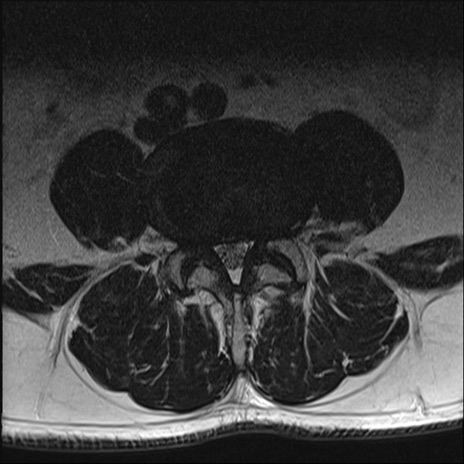

【整形】TIPS症例2 腰椎MRI T2WI(横断像)

【症例】70歳代男性

【主訴】左下肢痛

【現病歴】2週間前くらいから腰痛、左下肢痛あり。左臀部から大腿、下腿外側のしびれが常時ある。歩行とともに同部位の痛みあり。

【身体所見】Lasegue70-/60+、Bragard-/±、PTR ±/±、ATR -/-、IP 5/5、TA 5/4、TS 5/5、EHL 右第1足趾なし/3、FHL 5/5、hypersthesia(-)、足背動脈触知良好

異常所見と診断は?